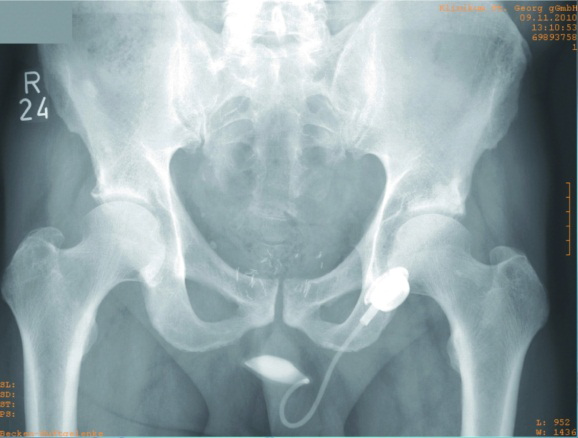

Our report relates to our clinical work and experience with the ATOMS® system (Figure 1 [Fig. 1], Figure 2 [Fig. 2], Figure 3 [Fig. 3]). We have been using the system for four years at our clinic and compared our findings with information obtained from other reported studies. Between 4/2010 and 04/2014, 36 patients received ATOMS® system implants at our clinic.

Figure 3: X-ray image of ATOMS® system implant